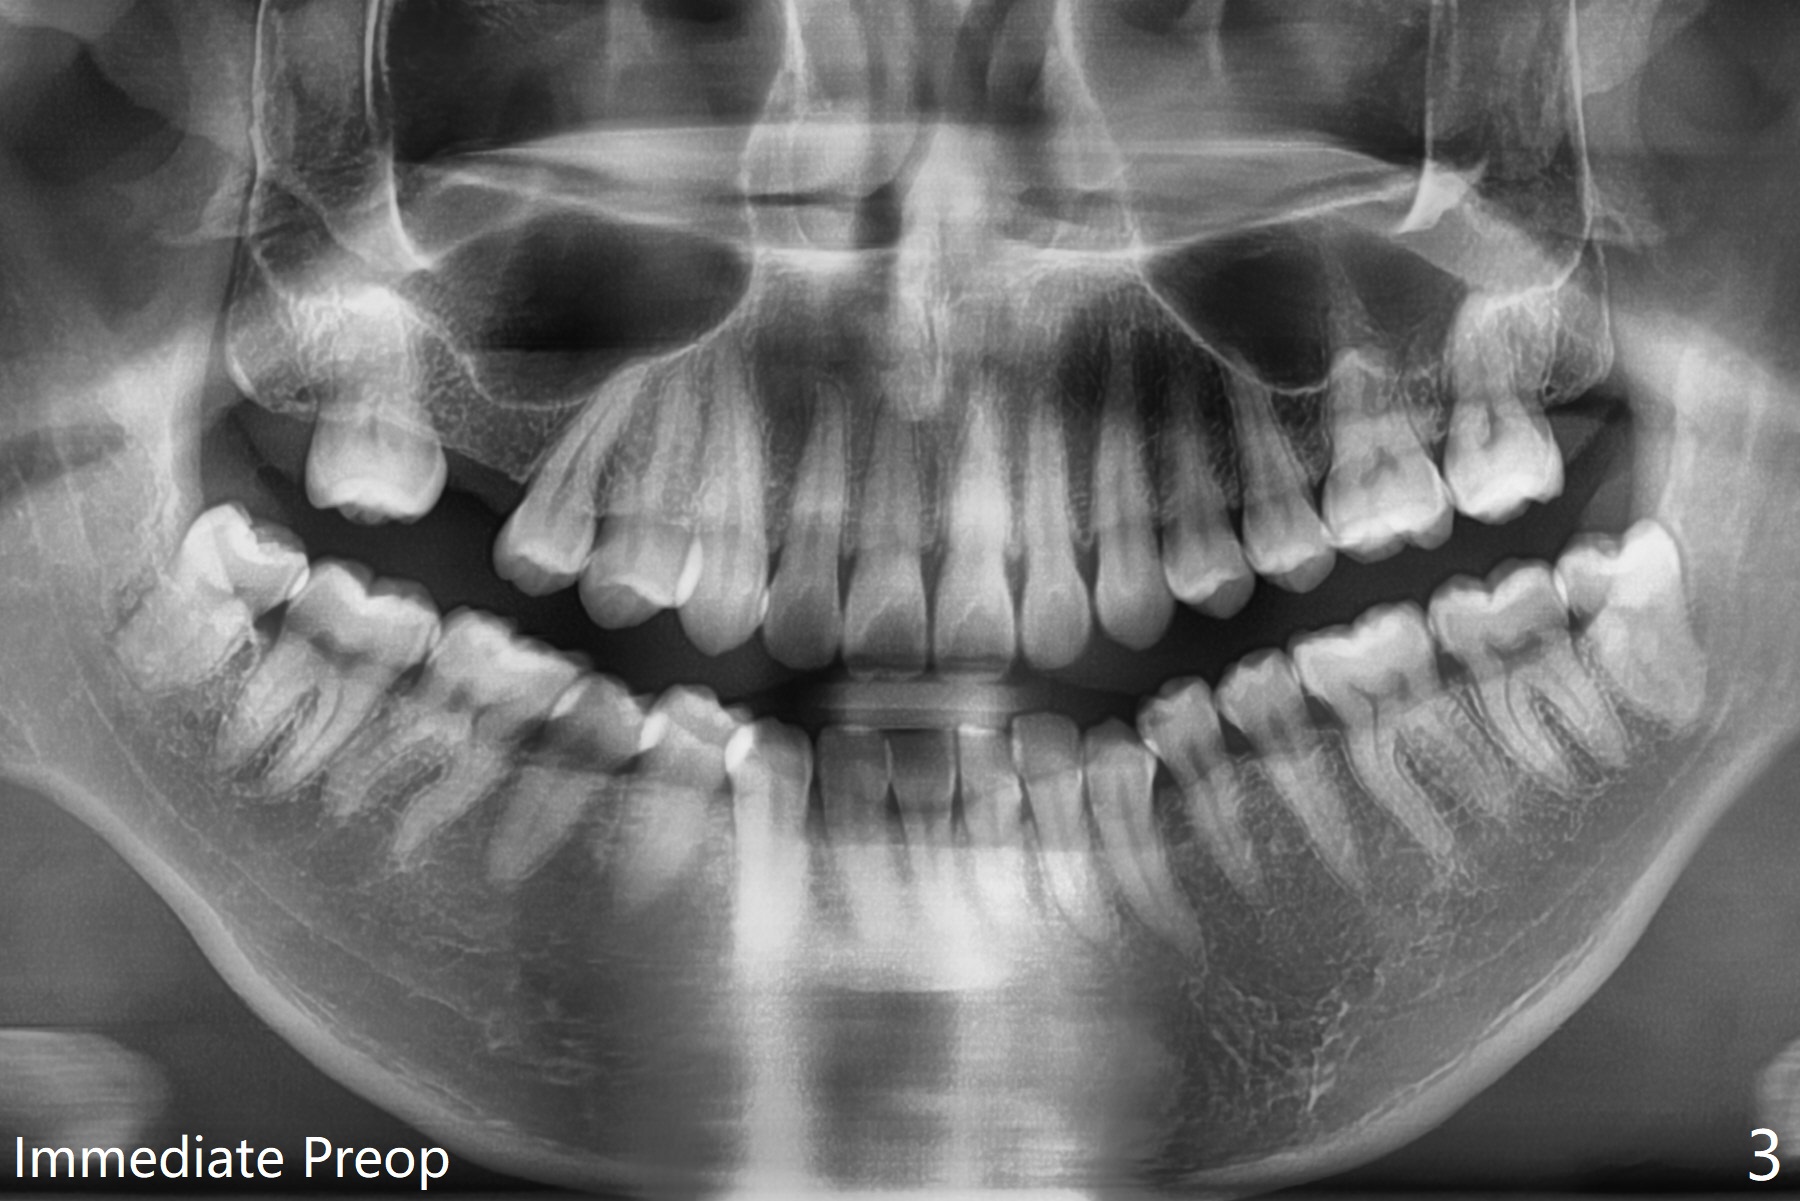

30岁男下颌深洗后,局部浸润麻醉,准备拔除颊侧阻生智齿(图一至三),每个牙槽窝放置0.5cc骨水泥(Bone Cement (Bond Apatite from Augma)),覆盖半块胶原塞,4-0铬羊肠线缝合(图四)。